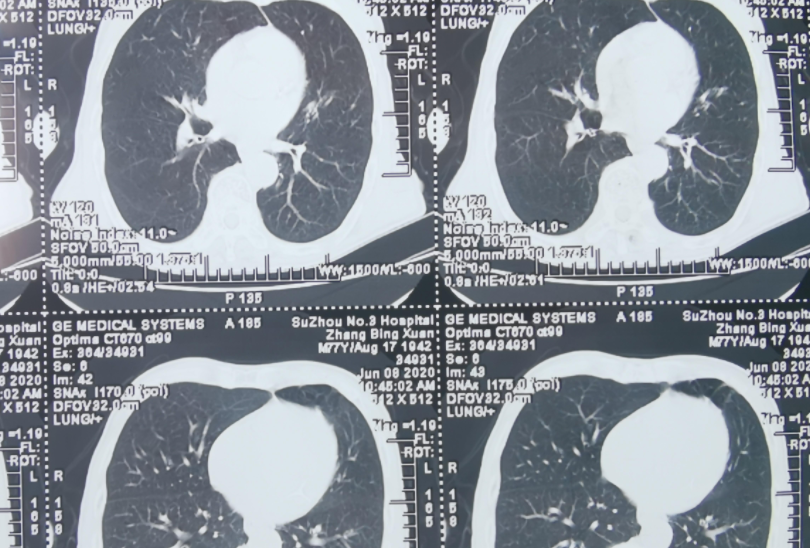

低剂量CT

普通CT平扫

高分辨CT

肺结节分析CT

增强CT

PET-CT